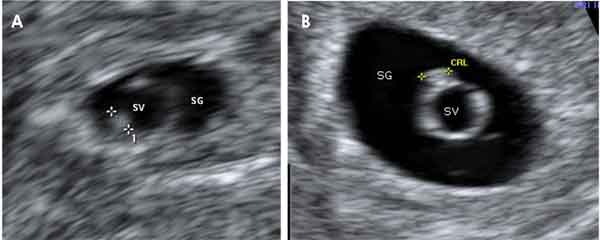

Embarazos de cinco semanas en imágenes

Podemos apreciar dos gestaciones de 5,1 (A) y de 5,2 semanas (B) en una ecografía de dos dimensiones. Se identifican dos embriones, de 1 y de 1,7 milímetros respectivamente (situados entre las marcas), en los que todavía no se aprecia latido cardiaco. Durante la quinta semana, el embrión aparece en íntimo contacto con el saco vitelino (SV), adosado a uno de sus bordes. El saco gestacional (SG) aloja ambas estructuras.